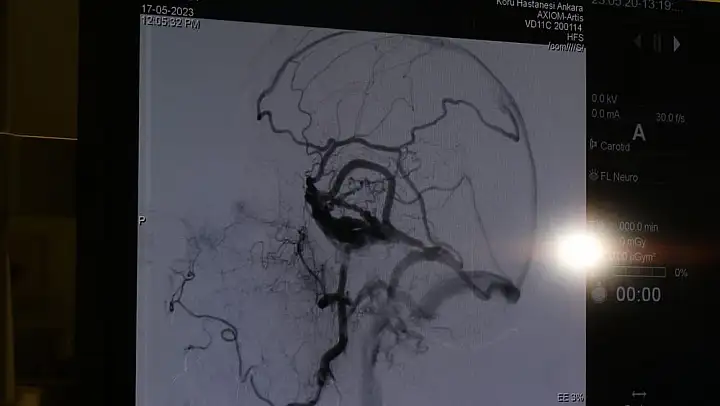

Özel Koru Ankara Hastanesi doktorlarından beyin ve sinir cerrahisi uzmanı Prof. Dr. Gülşah Bademci Adams Hakim Sendromu ya da daha yaygın olan adıyla erken bunamanın önüne geçmenin cerrahi müdahaleler ve düzenli kontrol ile mümkün olduğunu belirtti.

En çok uygulanan cerrahi yöntem, beyinde biriken sıvının karın boşluğuna aktarılmasıyla ilgili şant takılma ameliyatı olduğunu ifade eden Prof. Bademci'Ameliyattan sonra başarı oranlarımız yüzde 95 ile yüzde 99 arasındadır ..Özellikle hastalarımızın yürüme güçlükleri ve idrar kaçırma sorunları en erken düzelen bulgulardır. Hastalığın unutkanlık kısmı ise zaman içerisinde toparlanabilmektedir. Hastalık ile birlikte seyreden davranış bozukluğunun ise erken dönemde başarıyla düzeldiğini görmekteyiz. Hastanın kendisi bu sendroma sahip olduğunu kolaylıkla anlayamayabilir. Ama özellikle ailesi ve çevresi 40'lı 50'lili yaşlarda ki bireyin daha önceden olmayan özellikle öne doğru yıkılarak yürüme, idrar kaçırma veya mental yetilerde gerileme farkediyorsa ve çok ciddi bir unutkanlık ani olarak ortaya çıktıysa mutlaka beyin cerrahi bölümüne başvurmaları gerekmektedir' ifadelerini kullandı.